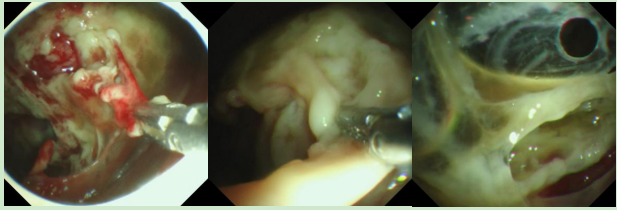

手术由儿科刘翔腾主任医师主刀,小儿外科、麻醉科团队全程护航,确保手术万无一失。术中,胸腔镜镜头清晰地展现出胸腔内的危急景象:大量脓液(脓苔)积聚,胸腔内黏连更是严重到近乎“锁死”。专家团队沉着应对,精准开展粘连带松解、脓苔廓清及引流操作,一步步为小骐“疏通”呼吸通道。